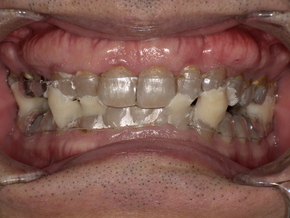

無呼吸と歯ぎしりの関係

無呼吸が起こると、体は呼吸を再開させようとします。その際に顎の筋肉が強く緊張し、歯ぎしり・食いしばりが起こります。

その結果:

-

歯のすり減り

詰め物・被せ物の破損

顎関節症

知覚過敏

を引き起こすことがあります。

つまり、無呼吸は全身だけでなく歯にも悪影響を与えるのです。